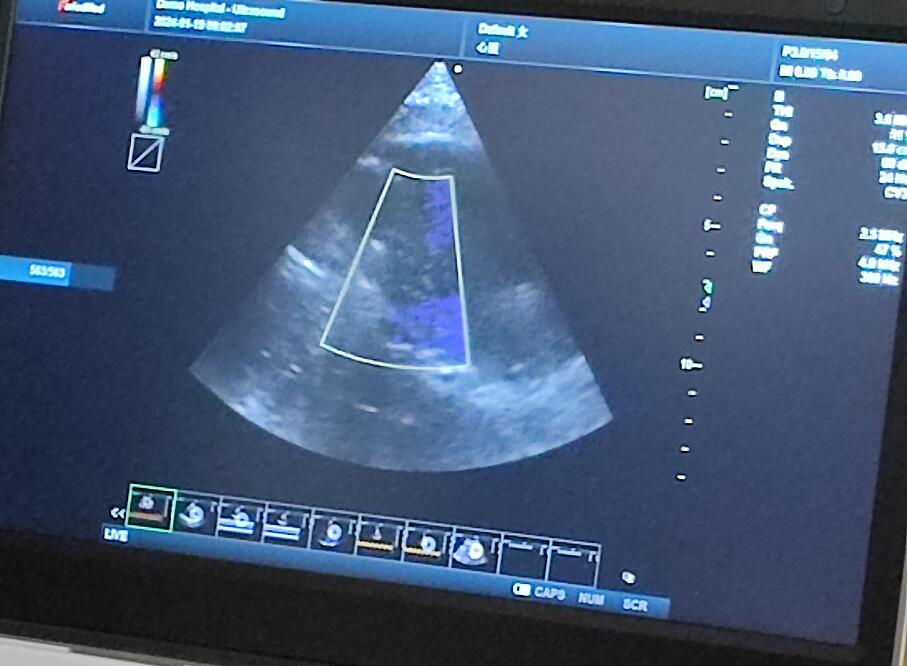

當(dāng)天的超聲培訓(xùn)現(xiàn)場氣氛熱烈非凡,來自普邁思醫(yī)療事業(yè)部的同仁們紛紛積極參與,滿懷期待地聚集在講臺周圍,他們的眼神充滿了對新知識的渴望和對技術(shù)提升的執(zhí)著追求。老師身邊里三層外三層圍滿了學(xué)員,大家或是聚精會神聆聽講解,或是踴躍提問,交流互動,濃厚的學(xué)習(xí)氛圍讓整個場地顯得熱鬧非凡,盡管空間狹小,但阻擋不住的是每一位參與者內(nèi)心深處對于專業(yè)技能提升的決心與毅力。

授課的專家老師被這股澎湃的學(xué)習(xí)熱情深深打動,她的臉上洋溢著欣慰和鼓舞的笑容。面對這樣一群如饑似渴的學(xué)子,老師更是傾盡全力,毫無保留地將自己豐富的臨床經(jīng)驗(yàn)和深厚的專業(yè)理論知識悉數(shù)傳授,詳細(xì)解答每一個問題,用心指導(dǎo)每一次操作演練。她表示,普邁思醫(yī)療事業(yè)部團(tuán)隊(duì)展現(xiàn)出的這種敬業(yè)精神和積極向上的風(fēng)貌讓她深受感染,還給予了他們高度評價和嘉許。